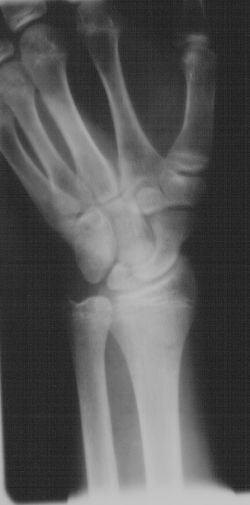

![]() |

| Twenty-five weeks post-injury and complete healing of scaphoid. Clinical images courtesy of Dr. Anthony Mauriello, Jr., MidState Orthopaedics, Lancaster, PA. |